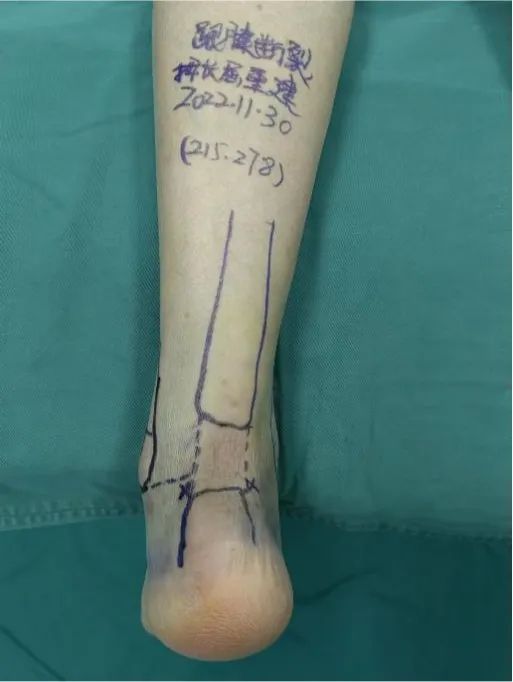

术前外观照,跟腱断端明显 术前MRI图像